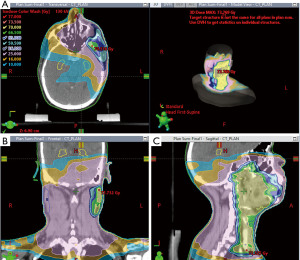

Radiotherapy planning

Planning and contouring were done using Varian Eclipse version 13.6 Treatment Planning System (TPS) (Version 8.6.17, Varian Medical System, Inc., Palo Alto, CA, USA). and dosimetric calculations were done using the anisotropic analytical algorithm (AAA). Dose evaluation to the hippocampus was done in previously planned and delivered IMRT patients, who were categorized as Group 1. Group 1 patients were then replanned by incorporating hippocampal dose constraints in the planning process, categorized as Group 2. The dosimetric parameters initially planned in Group 1 and re-planned in Group 2 patients were evaluated to determine whether the hippocampal dose constraints were achieved (Figures 2,3).